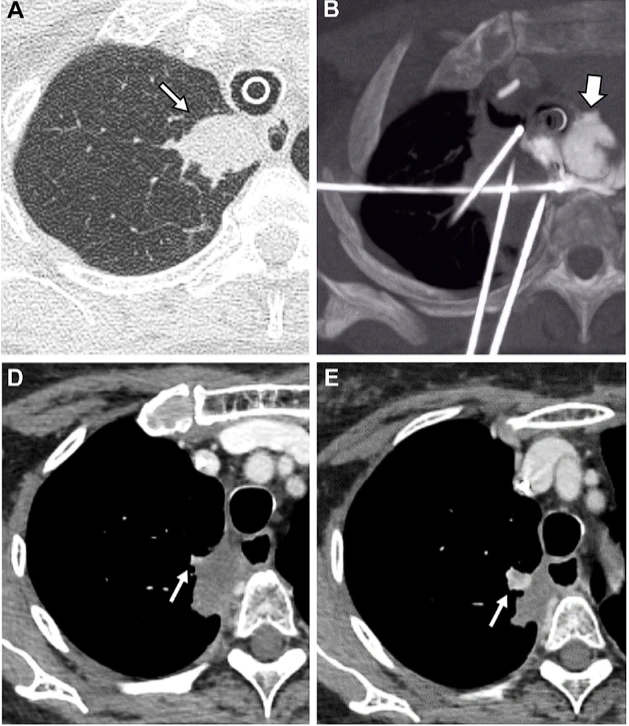

通过-140℃极冷冻结和+45℃快速复温的交替循环,在微创条件下精准杀灭肿瘤细胞,保护周围健康组织。

实时影像监测冰球范围,精确控制治疗区域,最大程度保护正常组织和重要器官